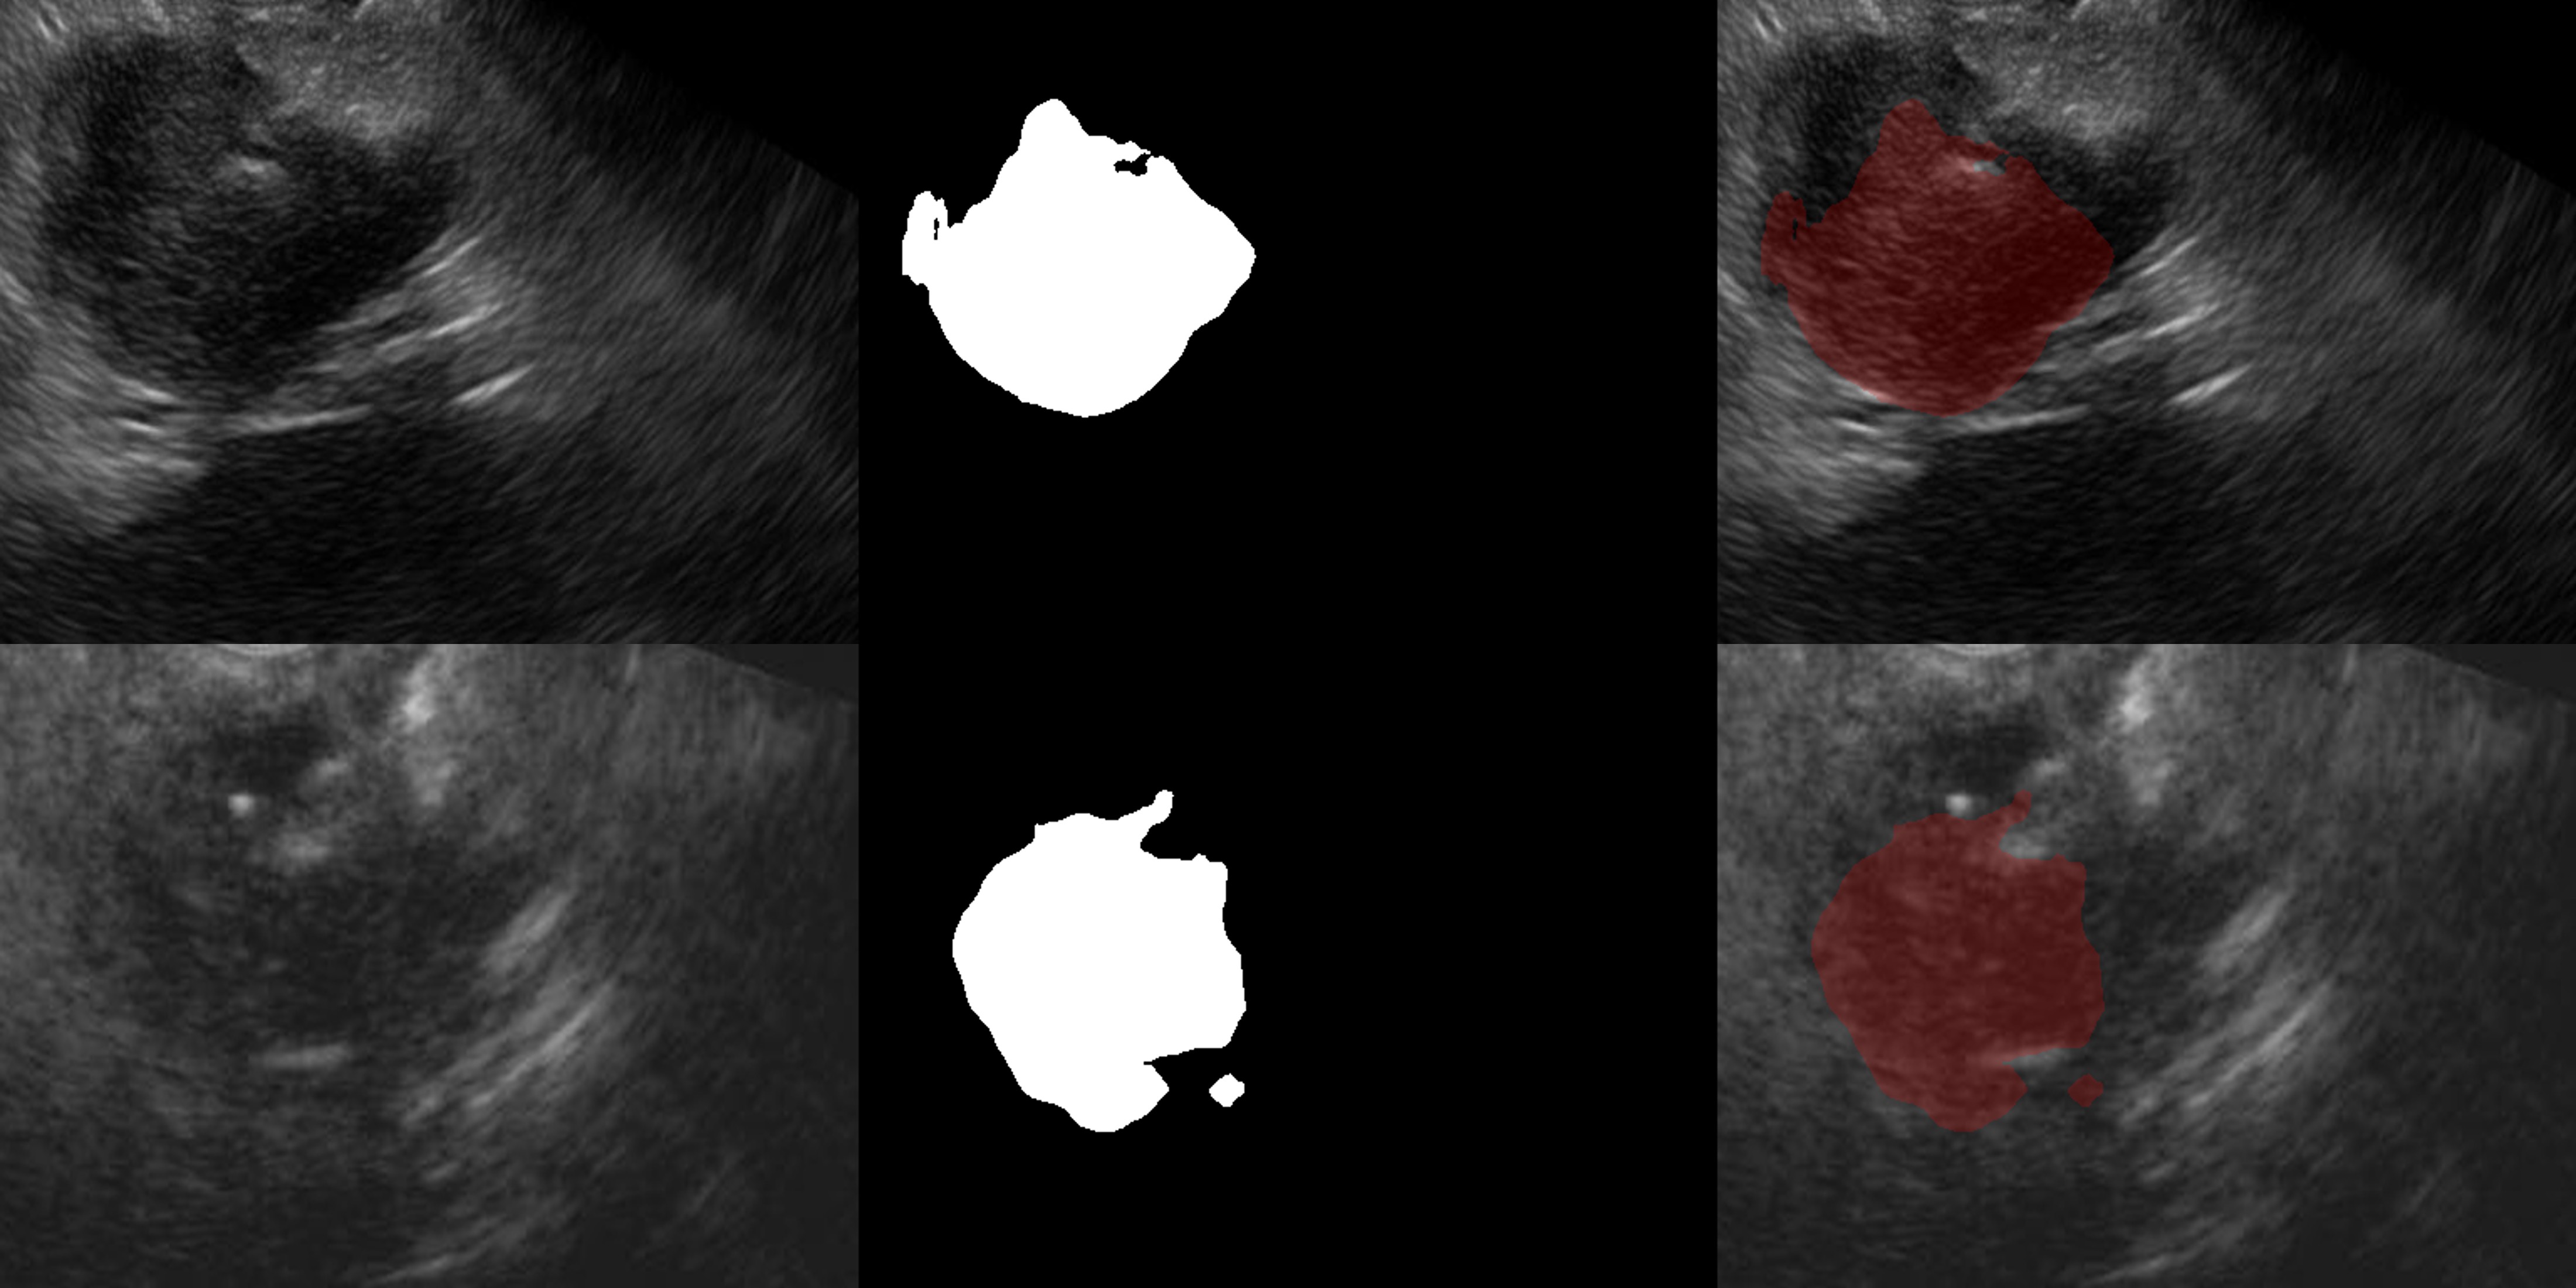

On the external test dataset of 350 images, the model achieved a DSC of 0.657 (95% CI 0.634–0.769) (Figure 1). The IoU for the test set was 0.614 (95% CI: 0.590–0.689). Sensitivity on this dataset was 71.8% (95% CI 69.1–79.3), while specificity was 97.7% (95% CI 95.1–99.2).

Figure 1: Segmentation visualization of pancreatic cancer in 2 patients with excellent segmentation by the DL model. Each row shows (left) input EUS image, (middle) ground-truth mask, (right) model prediction overlay (red). The DSC of the 1st patient (upper row) was 0.891 and that of the 2nd patient (lower row) was 0.905.

Failure analysis: The qualitative analysis of cases with complete failure (n=11) of segmentation with DSC << 0.1 showed a common pattern of lesions being smaller than 1 cm and showing subtle hypoechogenicity. Further cases where DSC << 0.5 were analysed. It was seen that these cases had ill-defined margins (Figure 2).

Figure 2: Segmentation visualization of pancreatic cancer in 2 patients with lower performance of the DL model. Each row shows (left) input EUS image, (middle) ground-truth mask, (right) model prediction overlay (red). In 1st patient (upper row) the mass has ill-defined boarders (compared with the case shown in Figure 1). The DSC in this image was 0.491. In the 2nd patient (lower row) the mass show subtle difference in the echogenicity compared to the background focally and has ill-defined boarders at places leading to the low Dice score (DSC: 0.413).